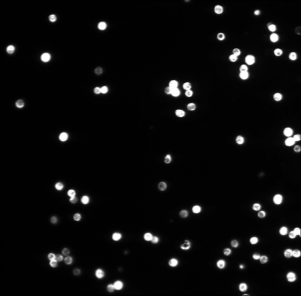

• [ZXSE07] Noha El Zehiry, Steve Xu, Prasanna Sahoo, and Adel Elmaghraby. Graph cut optimization for the Mumford-Shah model. In VIIP ’07 The Seventh IASTED International Conference on Visualization, Imaging and Image Processing, pages 182–187, 2007.